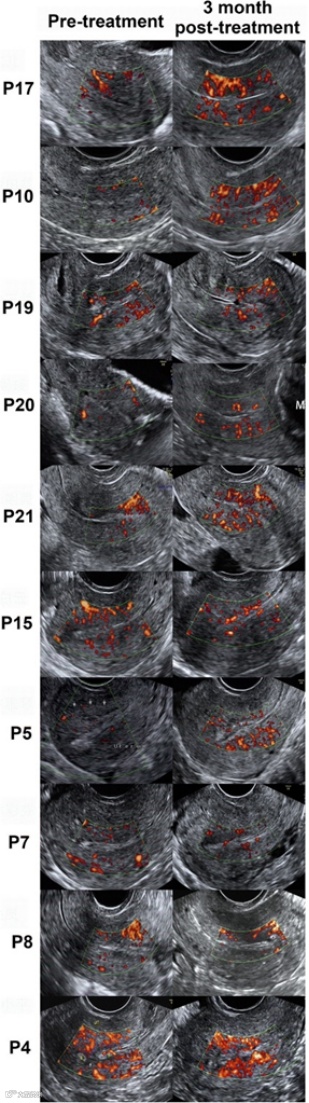

研究过程中,科学家们将1000万个(1×10^7个)脐带来源的间充质干细胞附着在胶原支架上,并在成功解除宫腔粘连后,将装载有干细胞的支架植入患者宫腔内。随后对所有受试者进行了为期3个月的严密随访,以详细监测子宫内膜厚度、宫腔粘连程度评分以及与子宫内膜再生相关的分子标志物变化。

研究结果表明,在接受UC-MSCs移植干预后,未观察到与干预直接相关的严重不良事件发生。经过3个月的干预及随访,患者的平均子宫内膜厚度相较于干预前有了显著增加,同时宫腔粘连的评分也有所下降。组织学分析进一步揭示,在干细胞疗法干预后,患者子宫内膜的增殖活性、分化状态以及新生血管形成能力均得到了积极改善。

患者干预前后超声对比